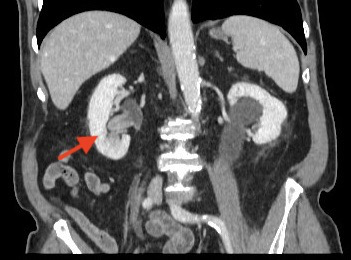

La urografía por tomografía computarizada (TC) – Uro TAC en nuestro país – es actualmente la técnica de imagen más precisa para el diagnóstico del CVUA, siendo de esta manera considerada como el estándar (Figuras 1 y 2)20. La TC puede ayudar además a predecir la etapa T del tumor primario (precisión hasta del 88%), siendo útil en la detección de metástasis regionales y a distancia (para esto último debe incluirse siempre una TC de Tórax)21. Sin embargo, presenta deficiencias en la detección de lesiones planas y tumores <3mm (hasta 40% de sensibilidad), casos en los cuales habitualmente es necesaria una evaluación endoscópica complementaria22. La TC con emisión de positrones (PET) constituye una alternativa promisoria para la evaluación de metástasis a distancia, con una sensibilidad superior a la TC convencional en estudios iniciales (85 vs. 50%), sin embargo requiere más validación para recomendar su uso rutinario en el estudio del CVUA23. Puede ser considerada en pacientes con función renal alterada que impida utilización de medio de contraste yodado.

Fig. 1. Imagen axial de TC con CVUA en cáliz inferior derecho